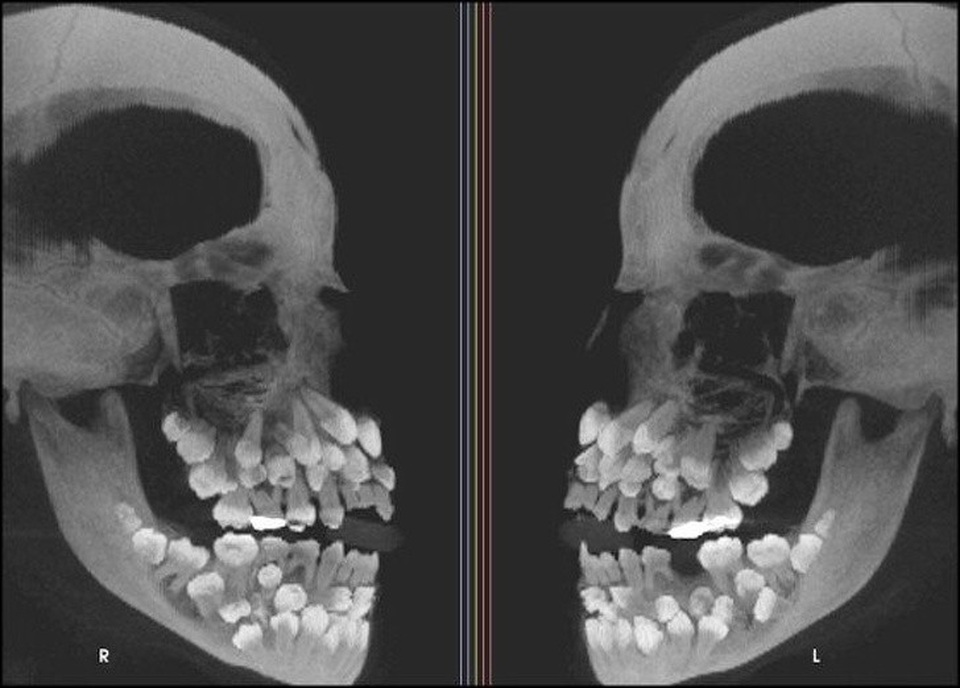

(Dân trí) - Hình ảnh chụp X-quang của những chủ thể đặc biệt như: một chú mèo đang mang thai, bộ phận cơ thể bị dị tật bẩm sinh hay thậm chí là bụng của cô bé nuốt nhầm chiếc bấm móng, được tổng hợp dưới đây, sẽ giúp bạn như bước vào một thế giới mà mình chưa từng biết!